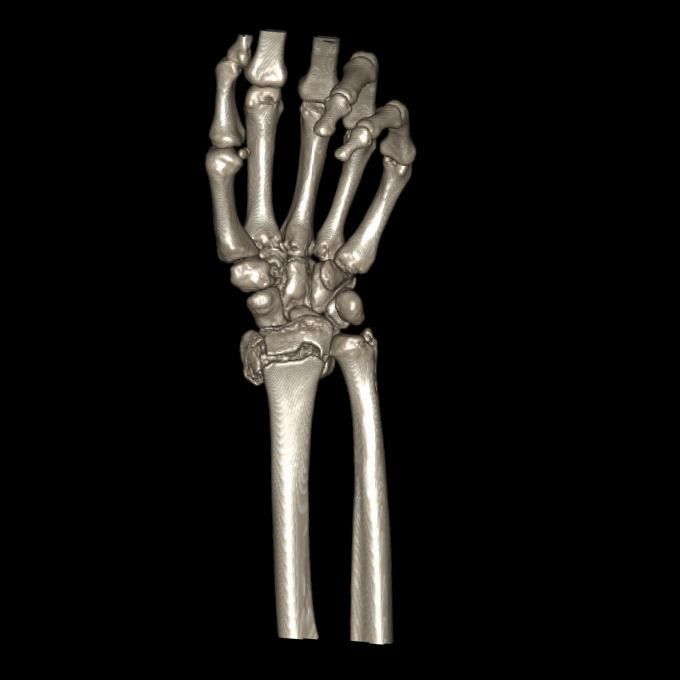

CT및 엑스레이는 12월 골절 당시 입니다

• 1번 째 사진

• 제공해 주신 영상들을 확인했습니다. MRI는 2023년 부분파열 당시 촬영본이고, 단순 방사선 및 CT는 2025년 12월 골절 당시 영상으로 이해하고 검토하겠습니다.

2023년 MRI 영상을 보면, 삼각섬유연골복합체(Triangular Fibrocartilage Complex, TFCC)에 전반적인 신호 변화와 함께 척골 부착부 근처의 손상 소견이 확인됩니다. 당시 봉합술을 시행한 것은 임상적으로 타당한 판단이었습니다. 이후 경과가 양호하다가, 2025년 12월 요골·척골 원위부 골절이 발생한 점이 현재 상황의 핵심입니다.

현재 상황을 종합적으로 보면, 폐쇄성 골절 후 금속 플레이트가 삽입된 상태에서 4월 이후 TFCC 부위 통증이 급격히 악화된 것은 단순한 염증 반응만으로 설명하기 어렵습니다. 골절 후 요척골 관계(distal radioulnar joint, DRUJ)의 정렬 변화, 플레이트 자체에 의한 기계적 자극, 또는 기존 봉합 부위의 재파열 가능성 모두를 고려해야 합니다. 플레이트가 있어 MRI를 아직 시행하지 못하셨다고 하셨는데, 이 부분이 현재 진단 판단의 가장 큰 제한점입니다.